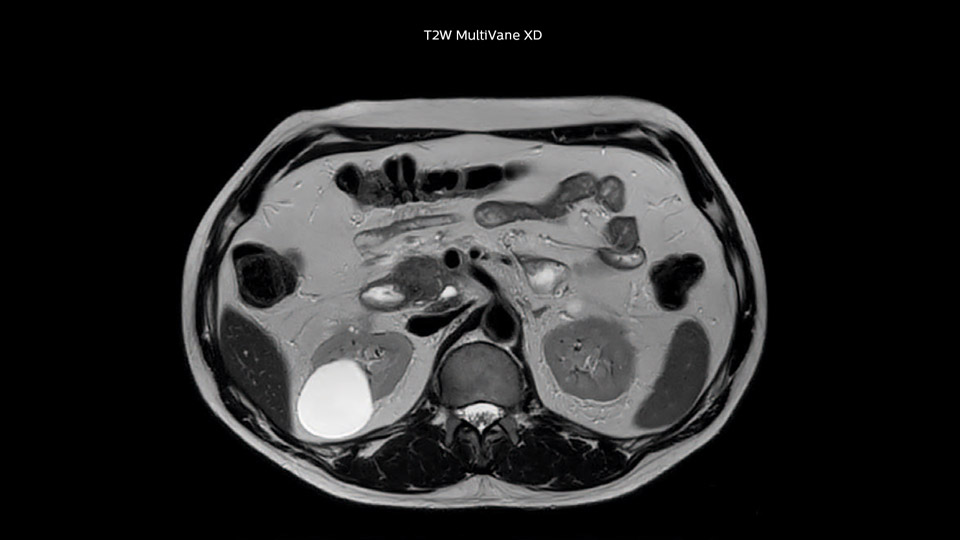

In this example the image quality of the MultiVane XD images is evidently better than in the images without MultiVane XD. Ingenia 1.5T with dS Torso coil solution.

“Our liver exams are quite fast,” says Dr. Baumann. “If the patient tolerates it, we use an arms-up position to reduce the FOV and speed up the exam with dS SENSE.” “We acquire one transversal high resolution T2-weighted sequence with 3 mm slice thickness, for example for pancreas or liver lesions. Then we also add a T2 fat suppressed MultiVane XD SPIR sequence. We perform these two routinely in our liver imaging. We use high dS SENSE factors to significantly shorten scan times to 2-4 minutes, which can improve our protocol; it’s a very robust scan.” “We include mDIXON for the dynamic sequences because of the robust and homogeneous fat suppression we get with that. We had been using eTHRIVE, but we are now quite happy with mDIXON. Sometimes we use a medication to calm the bowels, to further improve the image quality.”